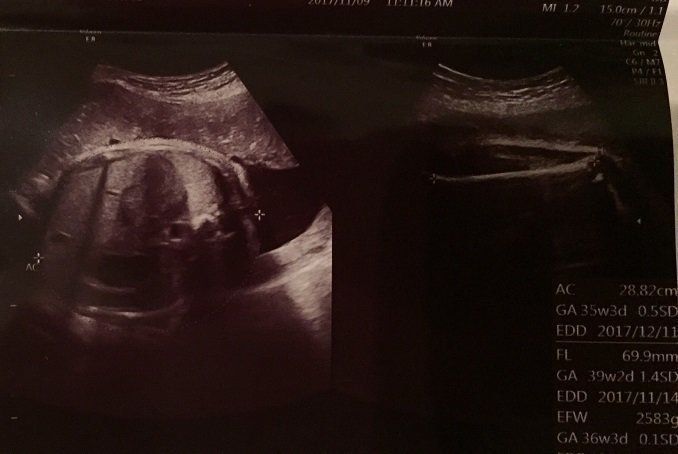

妊娠36週目のエコー写真 推定体重2800g。予定日には3000gを超える予想で少し緊張

この日のエコーが出産前最後のエコーということで,先生が身体の色々なパーツをていねいに写し出して見せてくれました。右上の写真では、あばらの骨がはっきりと見えています。

おなかを横から見た写真です。おなかが盛り上がるように膨らんでおり、赤ちゃんらしい丸いおなかだとわかります。右の写真は足の骨です。おなかまわりのサイズや足の骨の長さを丁寧にはかり、推定体重を教えてくれました。

先生には、これがおなかだと言われましたが、もう赤ちゃんが大きくなっているため、はっきりとは写っていません。長女のときもそうでしたが、エコーでお顔がゆがんではっきり写らない大きさになるともう出産が近いと実感します。